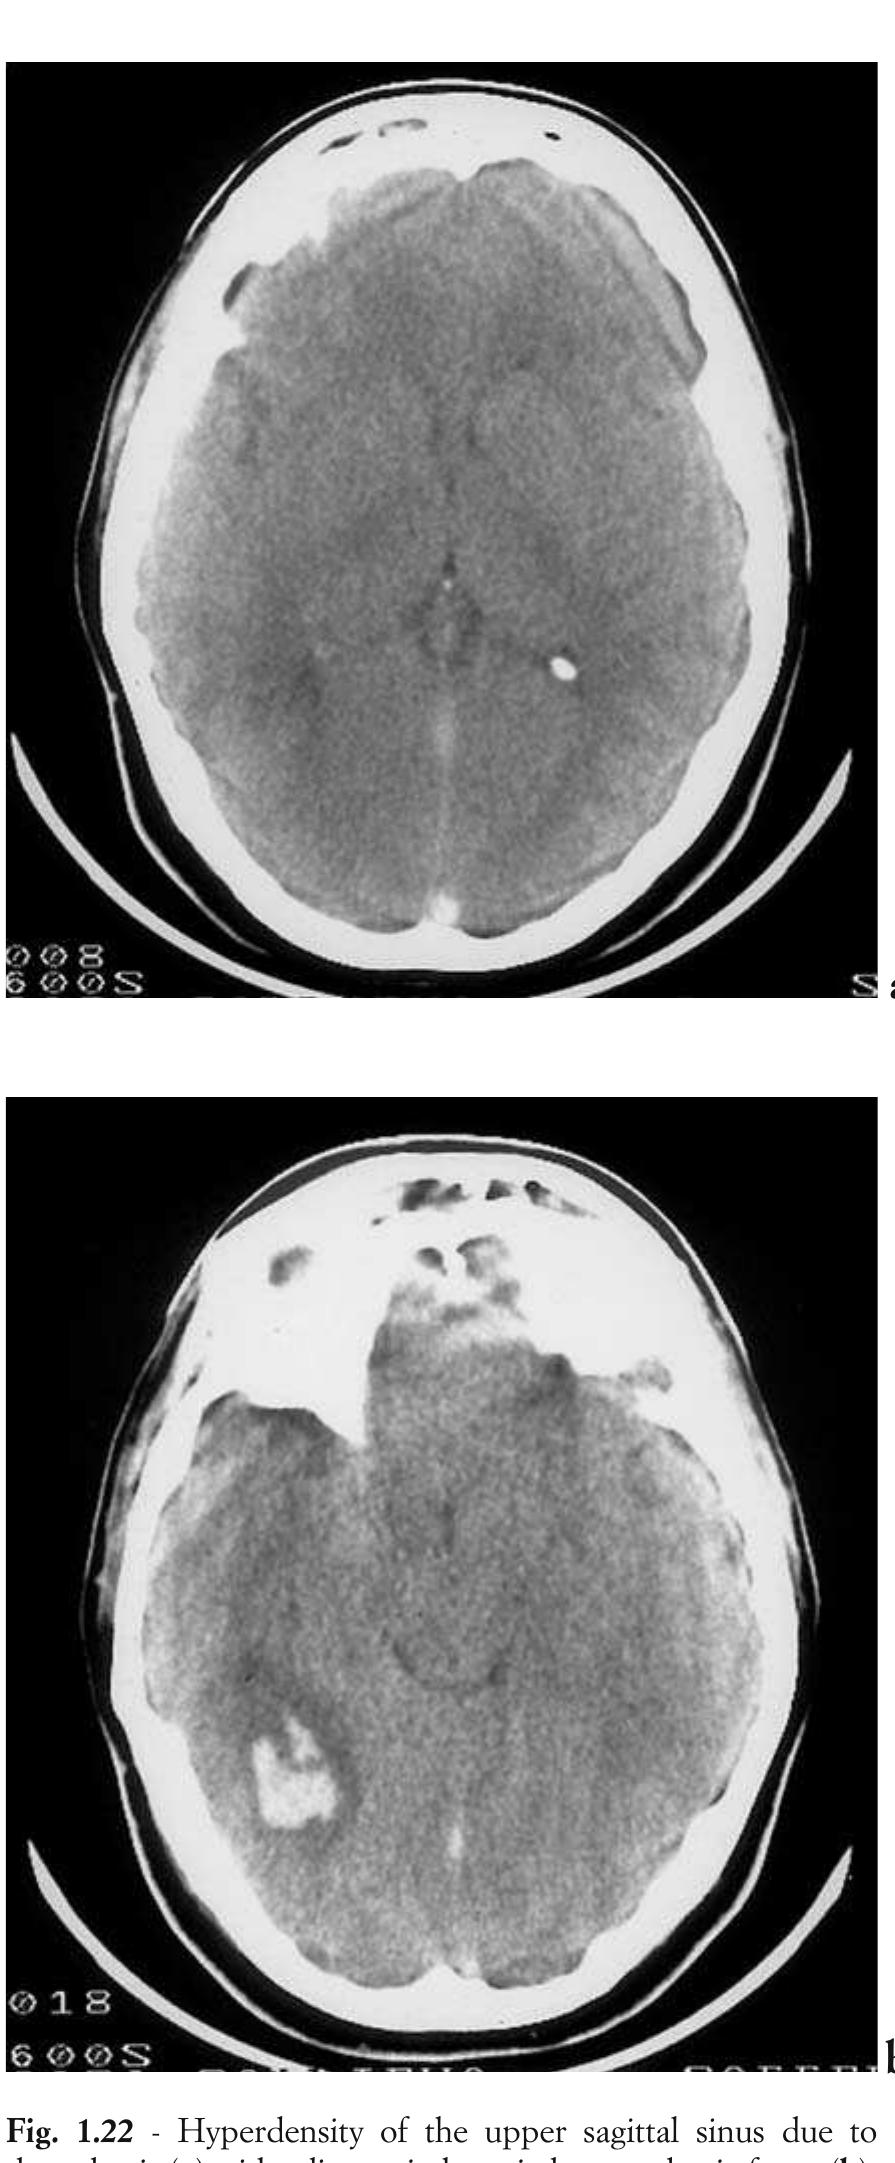

![convex lateral margin; however, in the presence of an SDH this margin becomes flattened, con- cave or irregularly distorted. If the cortico- medullary junction is not visible, a bolus injection of contrast medium administered during the scan may be useful in identifying the cortical surface and delineating the border of an isodense SDH. This image enhancement method can document Fig. 2.18 - Subdural haematomas. Axial and coronal CT shows small, chronic subdural haematoma over the convexity of the brain is observed which is better seen on coronal scans. [a) ax- ial CT; b) coronal CT].](https://figures.academia-assets.com/35610716/figure_156.jpg)